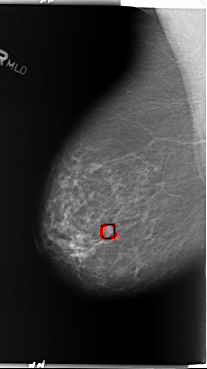

ics_version 1.0 filename B-3362-1 DATE_OF_STUDY 14 8 1997 PATIENT_AGE 77 FILM FILM_TYPE REGULAR DENSITY 2 DATE_DIGITIZED 4 6 1998 DIGITIZER LUMISYS LASER SEQUENCE LEFT_CC LINES 5936 PIXELS_PER_LINE 3304 BITS_PER_PIXEL 12 RESOLUTION 50 NON_OVERLAY LEFT_MLO LINES 5888 PIXELS_PER_LINE 3528 BITS_PER_PIXEL 12 RESOLUTION 50 NON_OVERLAY RIGHT_CC LINES 5896 PIXELS_PER_LINE 3040 BITS_PER_PIXEL 12 RESOLUTION 50 OVERLAY RIGHT_MLO LINES 5896 PIXELS_PER_LINE 3312 BITS_PER_PIXEL 12 RESOLUTION 50 OVERLAY |

FILE: B_3362_1.RIGHT_MLO.OVERLAY TOTAL_ABNORMALITIES 1 ABNORMALITY 1 LESION_TYPE CALCIFICATION TYPE PUNCTATE-PLEOMORPHIC DISTRIBUTION CLUSTERED LESION_TYPE MASS SHAPE ROUND MARGINS CIRCUMSCRIBED-ILL_DEFINED ASSESSMENT 3 SUBTLETY 3 PATHOLOGY BENIGN TOTAL_OUTLINES 1 BOUNDARY |